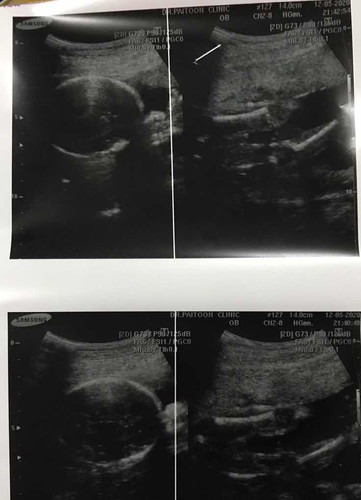

ในรูปไม่เห็นนะคะ คุณแม่ลองหา EFW ดูค่ะว่ามีมั๊ย ถ้ามีตรงนั่นแหละคาะ น้ำหนักน้อง

EFW = Estimated fetal weight คือ ค่าประมาณน้ำหนักตัวของทารกในครรภ์ ค่ะ

EFWคือน้ำหนักลูกจะขึ้นให้ที่แผ่นอัตราซาวค้ะ

พยายามส่องภาพแล้ว ไม่เห็นบอกไว้นะคะแม่

EFW ค่ะ